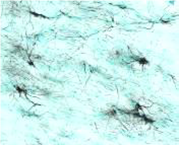

人神经干细胞(NSCs)移植入小鼠脑部,利用STEM系列抗体进行免疫组化染色鉴定。

在小鼠大脑的嗅球中,使用STEM101检测到移植的人神经干细胞(细胞核)。

在小鼠脑部海马体中,使用STEM121检测到移植进入的人神经干细胞的迁移和分化。

在小鼠脑中,使用STEM123检测到移植进入的人神经干细胞分化为星形胶质细胞。